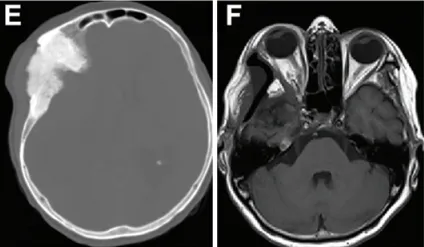

术前轴位计算机断层扫描显示反应性骨质增生及肿瘤累及骨骼的范围(图E)。术后MRI(图F)显示眼球突出显著改善(眼球突出指数=1.11)。

术后照片显示右眼眼球突出良好复位(图G)。